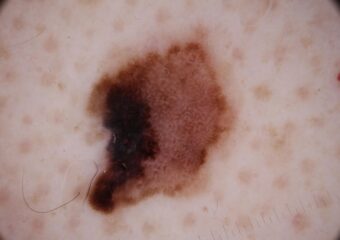

Actinic Keratosis (AK) Photos

Actinic keratosis on head or neck. Photo: International Skin Imaging Collaboration at isic-archive.com

Actinic keratosis on posterior torso. Photo: International Skin Imaging Collaboration at isic-archive.com